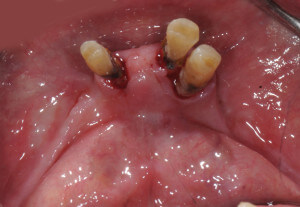

在下顎骨脊幾乎只剩一條線的狀況下,可以預見未來下顎活動假牙的穩定度一定很差.所以在治療的規劃裡,在下顎植了兩顆人工植體,利用植體去幫助假牙穩定.

完成的下顎活動假牙會有兩個墊圈,利用兩個橡皮墊的力量幫助假牙穩定

活動假牙的不穩定鬆動,常是造成老年人不愛配戴,導致牙口不好營養不良的主因.而假牙的鬆動通常來自於下顎,此時不必花大錢做全口植牙,我們可以僅僅藉助兩顆植體去達到穩定活動假牙的效果,通常治療完正常飲食都沒有問題,同時療程簡單效果良好.